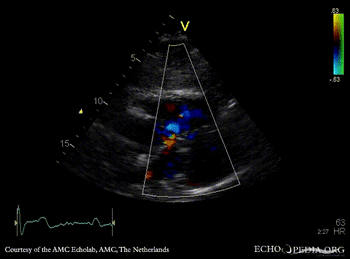

| PSAX: ASD type I | Subcostal view: ASD type I |